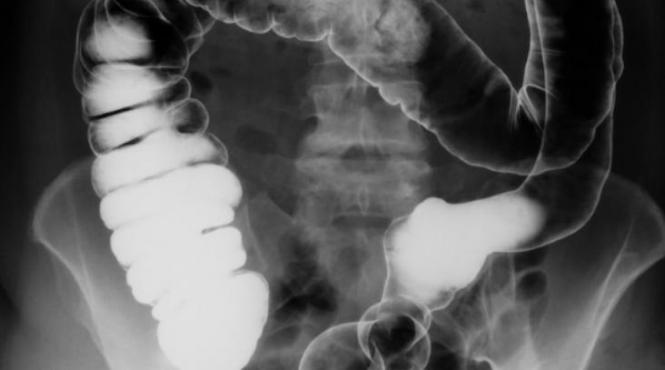

Medicii din California, în stare de ŞOC! Ce au găsit specialiştii în intestinul gros al unui bărbat întrece orice imaginaţie